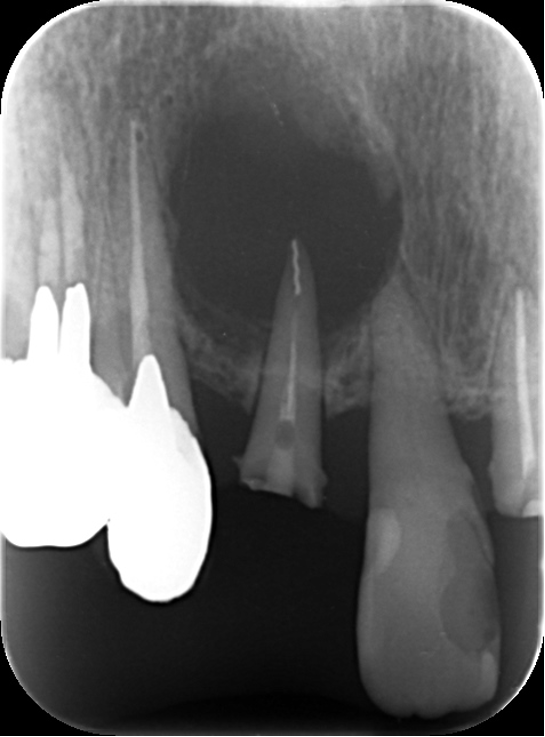

6ヶ月後のレントゲン(右側)を術前のレントゲン(左側)を比較します。かなり改善され骨が新生しています。順調です。